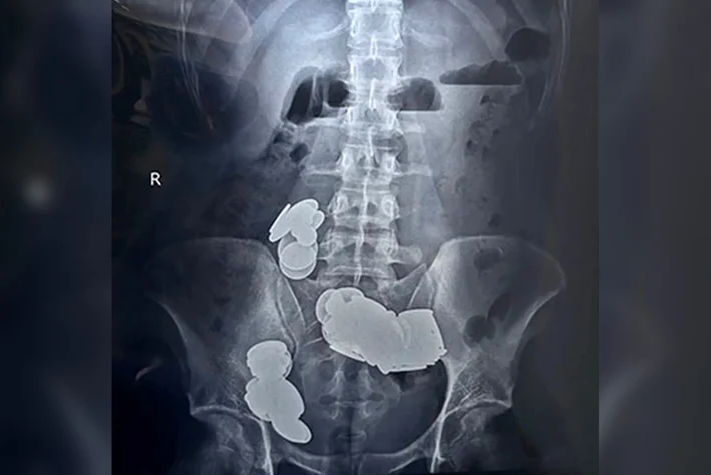

Diese absurde Idee hat ein 26-jähriger Inder wohl schnell wieder bereut. Um sich schneller in Topform zu bringen, schluckte ein Mann aus Delhi nicht weniger als 39 Münzen und 37 Magnete. Der kuriose Grund hinter der Aktion: Das enthaltene Zink sollte ihm beim Bodybuilding unterstützen.

Die Folgen waren aber katastrophal: Der junge Inder bekam starke Bauchschmerzen und musste sich immer wieder übergeben. Der Mann suchte deshalb ein Krankenhaus auf und wurde geröntgt. Was die Ärzte dann auf den Bildern sahen, machte sie fassungslos.

Die Münzen hatten sich in zwei getrennten Schleifen im Dünndarm verklumpt. Durch ihre magnetische Kraft verhakten sich die Teile und führten zu einem Darmverschluss. Der 26-Jährige hatte aber Glück im Unglück: Den Chirurgen gelang es, alle Münzen und Magnete zu entfernen – der Patient konnte das Krankenhaus nach einer Woche wieder verlassen.